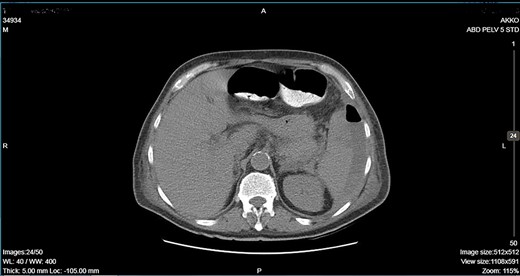

CT showing an important decrease of the abscess due to its rupture toward the peritoneal cavity and presence of air in the abdominal cavity.

A 64-year-old man presented to the emergency department with left pleuritic chest pain, anorexia and fever with rigors. His vital signs included a pulse of 130 beats/min, blood pressure of 108/51 mmHg, respiratory rate of 18 breaths/min, oxygen saturation of 95% and body temperature of 36.1°C. He had no relevant medical history. The patient was admitted to the hospital with the diagnosis of pneumonia based on his chest X-ray findings. The patient remained hemodynamically stable through the next day but developed a temperature of 39.2°C. A CT scan revealed a tumor of the splenic flexure that had invaded the spleen and pancreas via the transcoelomic route and created a subcapsular splenic abscess (Fig. 1). The CT scan also revealed splenic vein thrombosis located proximal to the tail of the pancreas. CT-guided percutaneous drainage of the abscess was scheduled for the following day. The patient’s clinical condition suddenly deteriorated and he became hemodynamically unstable. Abdominal distention with diffuse tenderness was identified via clinical examination, and laboratory tests revealed leukocytosis with a white blood cell count of 16.800/mm and anemia, with a hematocrit of 28.5%. An emergent CT scan revealed intraperitoneal rupture of the splenic abscess (Fig. 2). Intraoperative findings of an urgent surgical intervention included severe, diffuse purulent peritonitis with a large amount of pus mixed with blood clots in the peritoneal cavity that required cautious cleaning and thorough lavage. Furthermore, a large, hard, immovable tumor was identified in the splenic flexure of the colon. The tumor was tightly adherent to the spleen; we also noted the presence of intense inflammation and local fibrosis that extended to the surrounding tissues. En-block splenectomy and a wide left colectomy were performed followed by closure of the distant colon remnant using a linear stapler; furthermore, we also created an ostomy of the proximal colon remnant, similar to Hartmann’s procedure and drained the abdominal cavity. Transfusion of 600 ml of red blood cells was required. Extubation and postoperative recovery were uneventful, and the patient’s clinical status and parameters remained stable. Antibiotic treatment included meropenem 2 g thrice daily, metronidazole 500 mg thrice daily and amikasin 1 g once daily. The postoperative course was uneventful and the patient was discharged on postoperative day 12. Histopathological examination of the resected specimen revealed a 6 cm diameter perforated tumor adherent to an 18 × 13 × 6 cm spleen and a moderately differentiated grade 2 adenocarcinoma with infiltration to the pericolic fat. The resection margins were free of infiltration as were all of the 19 resected lymph nodes. A metastatic tumor, 2 cm in diameter, was identified in the spleen portal. The TNM stage was T3N0M1a (stage IVA disease), and the patient was referred to the Oncologic Department for adjuvant chemotherapy. He was administered eight cycles of Capecitabine that is changed into 5-fluorouracile + Oxaliplatin along with the necessary follow-up care. The patient has been disease-free for 2 years after the treatment.